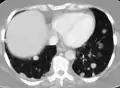

Pulmonary metastases shown on Chest X-Ray